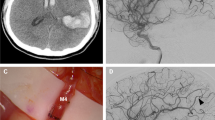

ICA terminus aneurysm (case #2)

A 44-year-old female presented with a 1-week history of severe headache. A head CT scan showed hyperdensity over the right carotid terminus region. Cerebral angiogram showed a dissecting pseudoaneurysm extending from the right supraclinoid ICA into the ICA terminus and occluding the origin of the anterior cerebral artery (ACA; Fig. 3a, b). This aneurysm represents a terminal aneurysm with the outflow from the ICA terminus only supplying the MCA territory. During surgery, flows were measured in the MCA branches and totaled 81 cc/min. The STA was dissected for the required length, and the cut flow was found to be 28 cc/min, which was inadequate for flow replacement; therefore, an interposition graft was felt to be necessary. Although the STA branch carried inadequate flow, the STA was truncated to its stump [3], which had a cut flow of 100 cc/min. Therefore, the interposition saphenous vein was placed as a short jump graft between the STA stump and an M2 branch. Following the bypass, the pseudoaneurysm was surgically trapped. Final bypass flow was measured to be 95 cc/min, and postoperative angiogram revealed filling of the full MCA territory (Fig. 3c).

A 44-year-old female with severe headache and acute dissecting pseudoaneurysm of the ICA terminus. a Anteroposterior view of right ICA angiogram demonstrating the dissecting aneurysm. b Anteroposterior view of the left ICA angiogram demonstrating occlusion of the origin of the A1 and cross-filling of the right ACA. c Anteroposterior view of postoperative angiogram demonstrating the vein interposition graft between the STA stump and the MCA